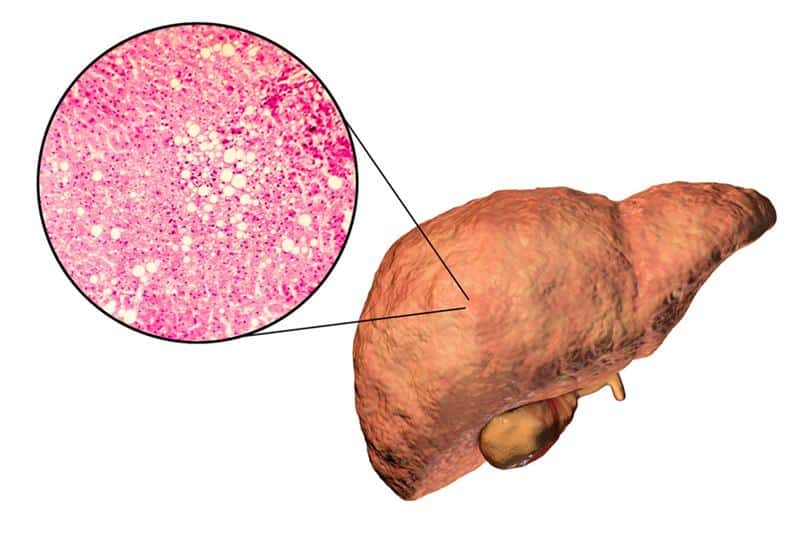

A Literature Review on Fatty Liver Disease

In the structure of chronic liver diseases, the most common are non-alcoholic fatty liver disease (NAFLD), alcoholic liver disease (ALD),...Read More